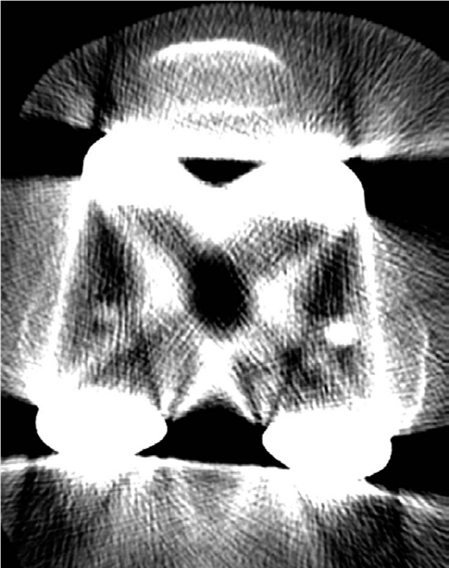

KNEE Structured oralexamination question9: Malalignment of total knee replacement (TKR) components EXAMINER :…